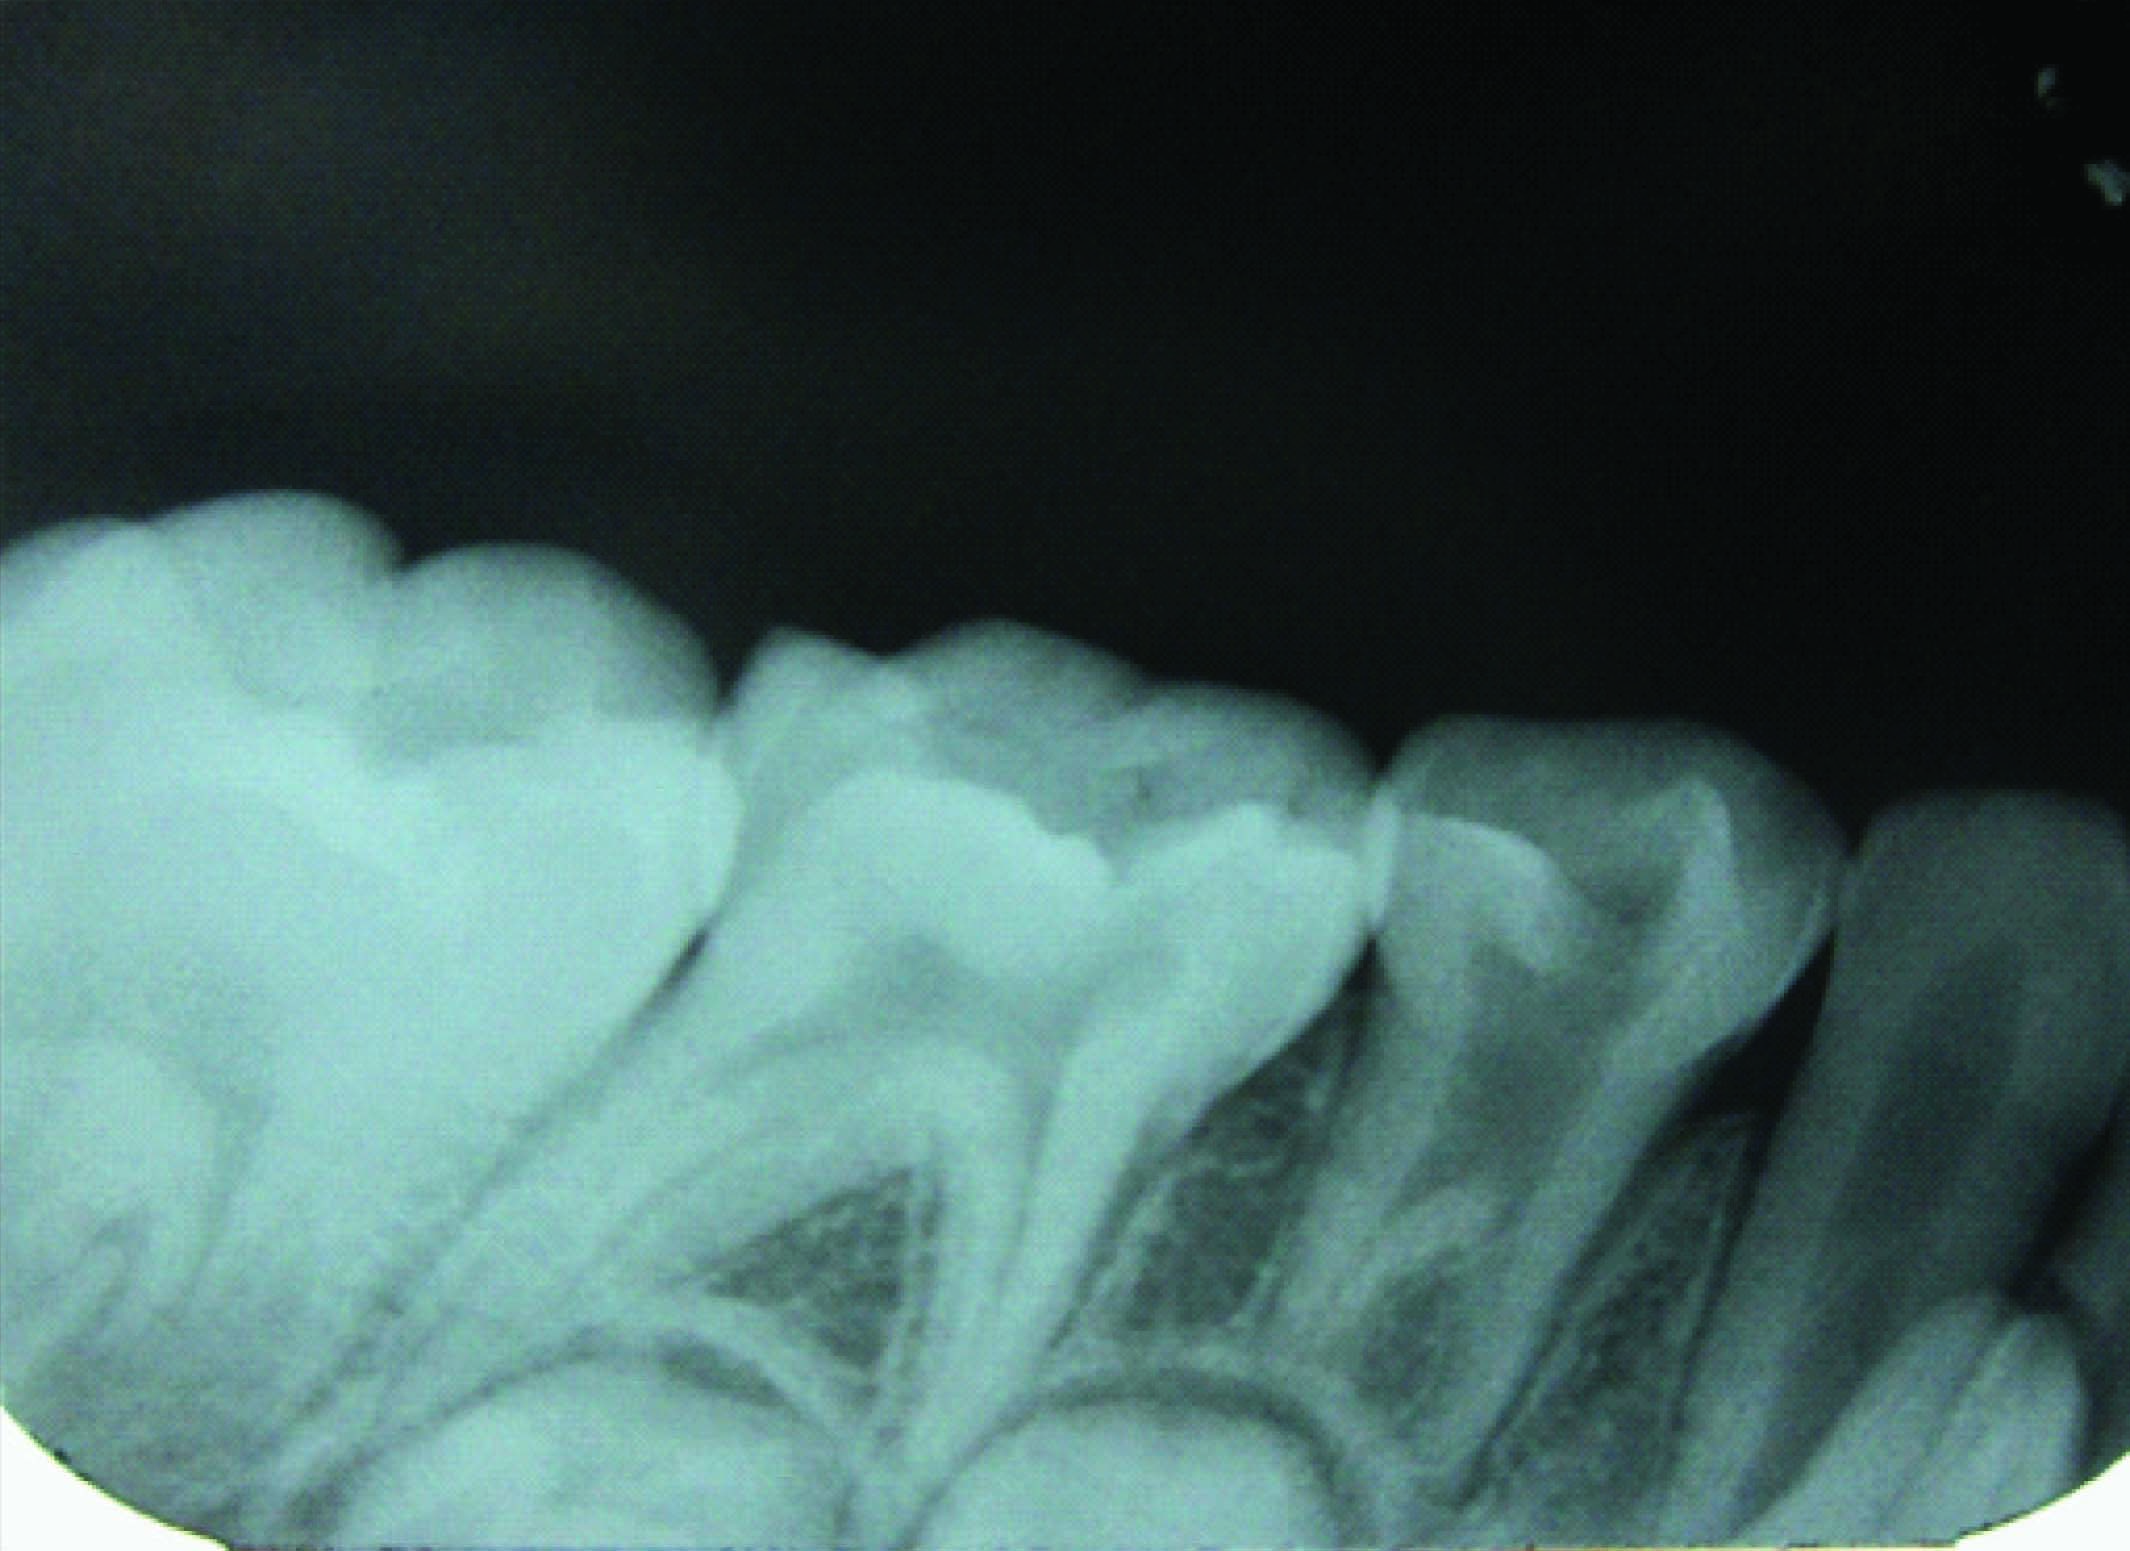

Extraction followed by space maintainer was planned for 64 and 85 [Table/Fig-4, 5]. On further examination of the patient’s sibling’s similar characteristic radiographic finding of taurodontism was discovered. IOPA of 84, 85 region of brother [Table/Fig-6] and IOPA of 84 region [Table/Fig-7] of sister exhibited taurodontic characteristic. Suspecting this the mother was also subjected to radiographic procedure who to our great surprise exhibited taurodontic appearance of a previously endodontically treated 36 [Table/Fig-8].

IOPA shows large pulp chamber suggesting taurodontism of 84, 85 of the patient’s 5 year old brother,